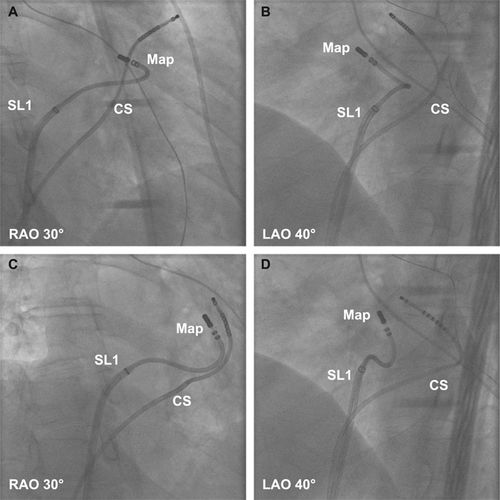

Ablation in coronary cusps - Aware of relationship to coronaries

cor_angio.jpg